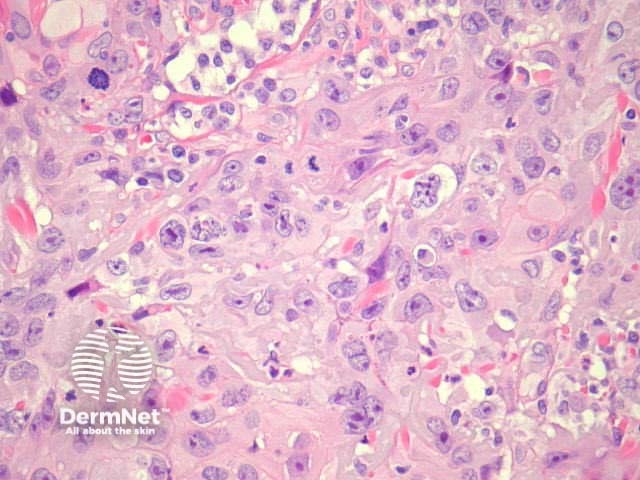

Typical SCC has nests of squamous epithelial cells arising from the epidermis and extending into the dermis (figure 1). The malignant cells are often large with abundant eosinophilic cytoplasm and a large, often vesicular, nucleus. Variable keratinisation (keratin pearls etc) is present (figure 2).

Grading of SCC depends on how easy it is to recognise the characteristics of squamous epithelium (eg. intracellular bridges, keratinisation), pleomorphism and mitotic activity. There is considerable inter-observer variation in grading SCC.